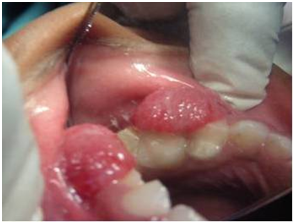

A 8year old boy complaints of over growth in the mouth pertaining to upper left anterior region which bleeds frequently and interfered with eating and brushing. His mother gives a history of trauma during tooth brushing. He noticed the growth two months back which started as a size of peanut and gradually increased to reach the present size. His medical history and family history was non-contributory. No abnormality detected on extra oral examination and intra oral examination revealed a single growing exophytic, lesion was pedunculated with stalk, which was measuring 2.8×2.8×0.9cms in the left upper anterior to the posterior region, and it was attached to the marginal gingival in between the left primary canine to the first and second primary molars (Figure 1). It was oval in shape, has a smooth surface , reddish in color, pedunculated, bleeds on probing and it covers buccal surfaces of the teeth. These findings were confirmed by palpation of the lesion. Furthermore, there was no caries and absence of mobility of the involved teeth and he was in mixed dentition period. Oral hygiene status was seems to be poor. Blood picture shows all the values are within the normal level. Based on the history and intra oral findings, provisionaliy it was diagnosed it as a pyogenic granuloma.

Figure 1 Intra oral picture showing the lesion of the maxilla.